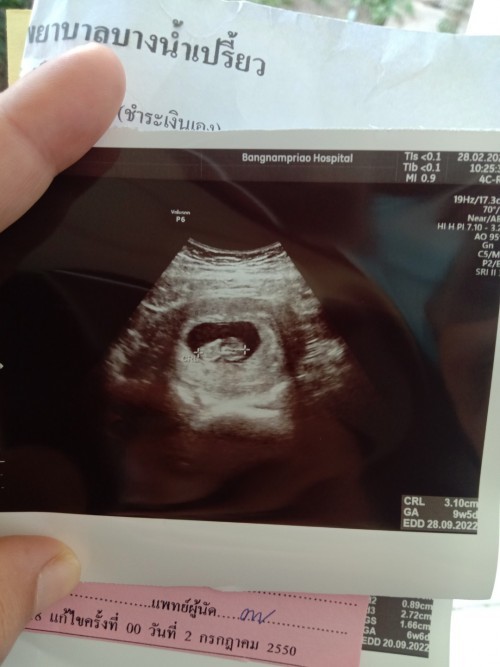

อายุครรภ์ 10w ค่ะ

น้องยาวได้ 3.6ซ.ม.